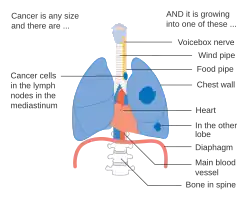

Stage IIIB lung cancer

Stage IIIB lung cancer -

Stage IIIB lung cancer

Stage IIIB lung cancer -